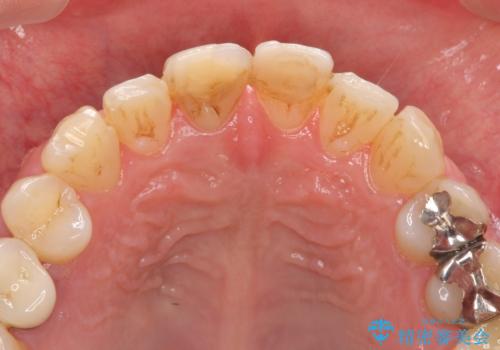

- 前歯の変色が気になり審美障害の改善を求めて来院されました。

根管治療に伴う歯の色調変化はよく見られる所見です。

セラミッククラウン製作を行い審美性の改善を計画します。

- 15.4万円(仮歯・ファイバーコア・ジルコニアクラウン)費用は治療当時の料金となります